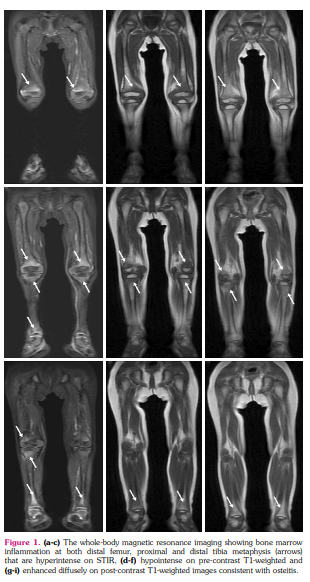

The sister of Patient 1 who was 18 months old presented to our department with recurrent joint and bone pain, fatigue, and anemia during the last six months. There were no skin findings. Physical examination was unremarkable. The APRs were elevated at the time of admission (ESR 120 mm/h and CRP 14 mg/dL). Severe neutropenia (600/mm3) with normal WBC count, microcytic anemia (hemoglobin 8.6 mg/dL), and thrombocytosis (700x103/mm3) were detected. The bone marrow assessment revealed a normocellular bone marrow with megaloblastic changes. The WBMSS-MRI demonstrated osteitis at the distal femur, proximal, and distal tibia, bilaterally (Figure 1).